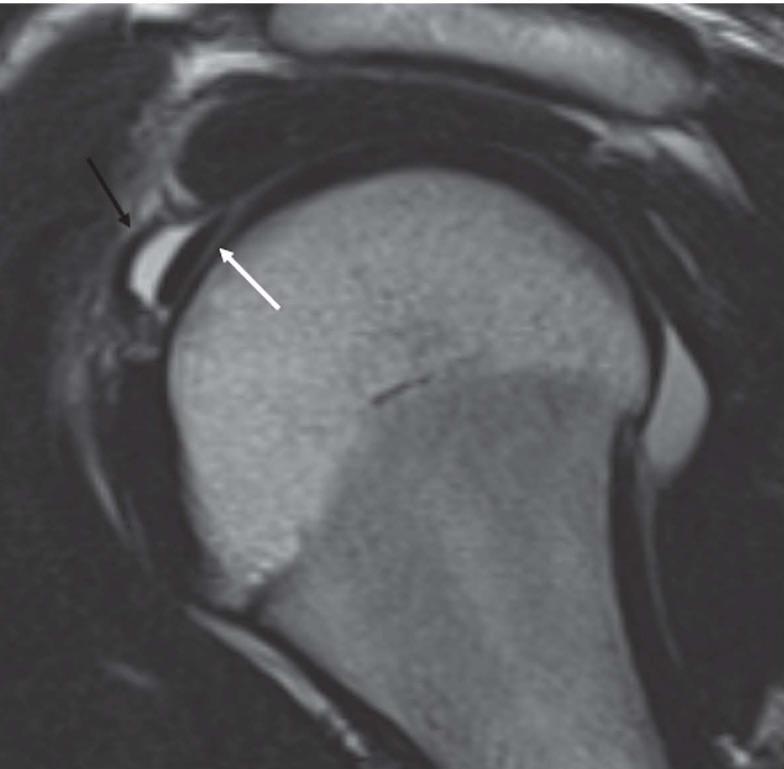

The aim of this is article is to provide an  imaging review of normal anatomy, most common anatomical variants and pathologies of the long head of the biceps tendon (LHB) encountered during the daily practice.

本文的目的是对日常实践中遇到的肱二头肌长头肌腱(LHB)的正常解剖结构、最常见的解剖变异和病变进行影像学综述。